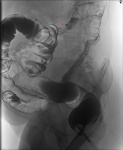

Спазмы. Один участок в глаза бросился, но  нестойкий он.

Может быть вы правы, а может быть и нет (создаётся впечатление, что он всё-таки повторяется на серии снимков, а виден не всегда, потому что проекции разные). Я б ы всё-таки рекомендовал фиброколоноскопию, с обозначением зоны интереса.

На самом первом снимке все напрягающие участки кишки хорошо просматриваются . Проствет не изменен.Поэтому видимые сужения расцениваю как сегментарные спазмы.